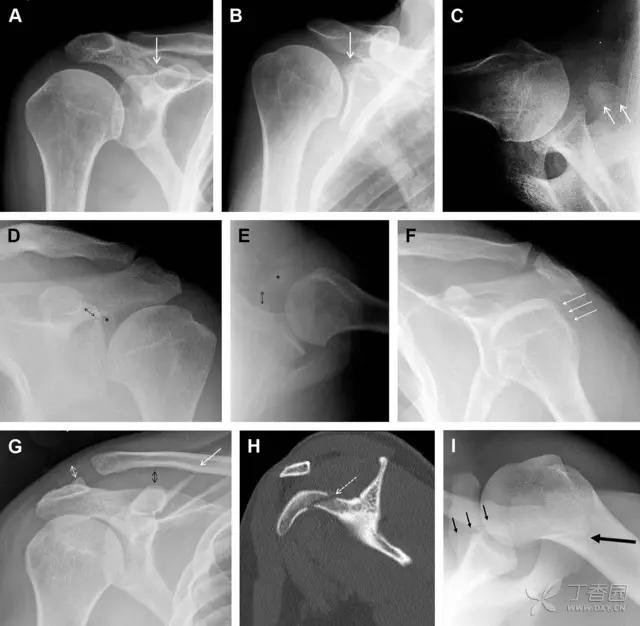

26 喙突骨折

喙突骨折可发生于直接*力暴**、肩关节脱位过程的肱骨头撞击、以及撕脱骨折(肱二头肌短头、喙肱肌)。

其中喙突基底部骨折最多见,常发生于直接*力暴**或肱骨头前脱位,骨折可延伸至关节盂。

而撕脱骨折多为喙突尖部的骨折。需要加拍腋位和 Stryker 位片(X 射线束以喙突为中心并头倾 10°,手臂外展,这样可以避开骨性结构的阻挡)。

有时,负重位片可发现并存的肩锁关节脱位,将有助于诊断。

图 4 喙突骨折。66 岁男性患者,猎枪射击后右肩前方疼痛。(A)内旋位前后位片投影隐约可见喙突基底部骨折(白色箭头),(B)外旋位前后位片投影结构存在重叠,(C)腋位投影时可良好显示。(D~F)喙突骨折伴 Hill-Sachs 损伤:肩关节脱位后慢性疼痛,喙突骨折块(*)向前外侧移位(双箭头),在外旋前后位(D)及腋位(E)片上均可显示,在内旋位前后位(F)片上,喙突被遮挡,但可见肱骨头 Hill-Sachs 损伤。(G、H)喙突骨折伴肩锁关节脱位,肩锁关节分离(白色双箭头),而喙锁间距正常(黑色的双箭头),应警惕喙突骨折。(I)喙突与肩峰骨化中心:对于未成年人,喙突与肩峰骨化中心可同时存在,易与骨折混淆,此时,拍对侧的 X 线片对比将有助于诊断。

27 肩峰骨折

肩峰骨折为高能量损伤,多由直接*力暴**导致,好发于中青年患者,多伴有肩关节其它结构损伤。有必要拍摄 Rockwood 位(前后位片,X 线束尾倾),特别有利于显示肩峰下部及肩峰下间隙。

图 5 肩峰骨折。内旋位前后位(A)片上,骨折线几乎被喙突完全遮挡, 但是在标准前后位(B)和腋位(C)片上可见骨折线